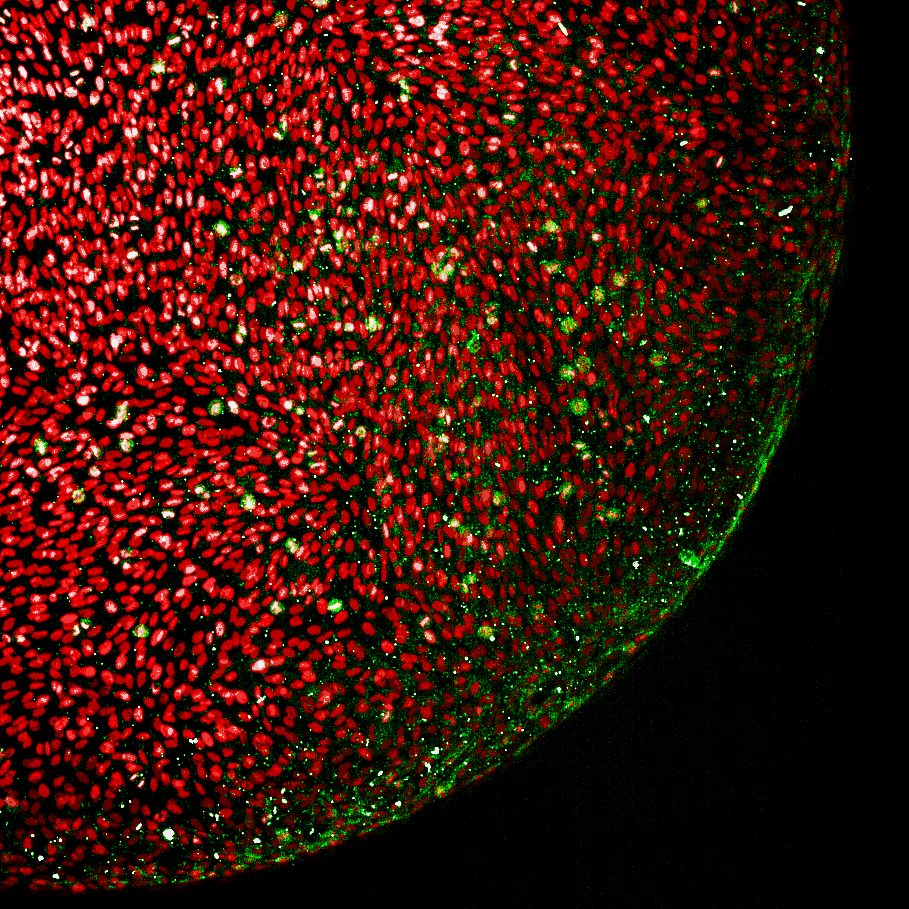

Our 3D patient-derived glioblastoma platform is built on starPEG–glycosaminoglycan hydrogels that recreate brain-like extracellular cues, enabling high-throughput functional drug testing and drug-response profiling in a 384-well format with high-content omics and phenotypic readouts.

Diagram showing a high-throughput screening system for patient-derived 3D glioblastoma models, including primary patient cells, a liquid handling system, 384-well plates with hydrogel components, and an imaging process for quantification and comparison of drug responses with 3D graphics of sample images and analysis results.